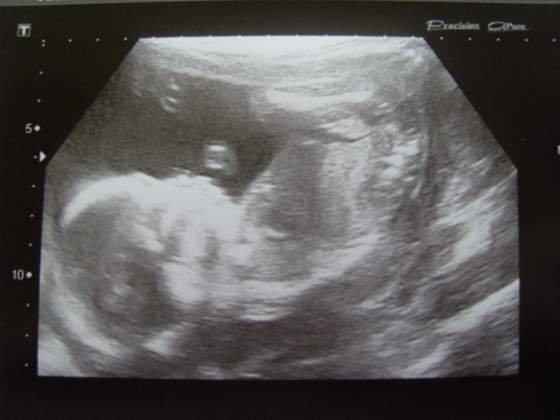

Od niego będzie zależało, czy urodzę normalnie, czy będzie przymusowa cesarka...